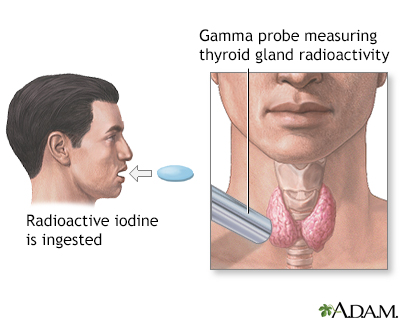

Radioactive iodine uptake test Wikipedia shop, Radioactive iodine uptake Information Mount Sinai New York shop, Radioactive Iodine Uptake Test shop, Radioactive Iodine Uptake Testing Background Indications shop, Radioactive Iodine Uptake Test Risks Preparation and Results shop, Radioactive Iodine Uptake And Scan My Endo Consult shop, Radioactive Iodine Columbia Surgery shop, Radioactive Iodine Uptake Test MEDizzy shop, Radioactive Iodine RAI Uptake THANC Guide shop, A radioactive iodine uptake test A B C and D demonstrate shop, StudyXing Medicine on X shop, Radioactive iodine uptake RAIU test shows large right and left shop, Radioactive Iodine Therapy to Treat Thyroid Cancer shop, AMBOSS Step2CK quiz time Can you distinguish the shop, Thyroid Scintiscanning an overview ScienceDirect Topics shop, Hyperthyroidism and Thyrotoxicosis Workup Approach Considerations shop, Radioactive Iodine Uptake Test Health Library NewYork Presbyterian shop, Twenty four hour radioactive iodine 123 uptake test. The images shop, Graves Disease Endocrine Medbullets Step 2 3 shop, Radioactive Iodine Uptake Testing Background Indications shop, Radioactive Iodine Uptake Test Risks Preparation and Results shop, Hyperthyroidism Diagnosis and Treatment AAFP shop, Thyroid Cancer SNMMI shop, Radioactive Iodine RAI Uptake THANC Guide shop, Thyroid Scan and Uptake shop, Determination of remnant thyroid volume comparison of shop, Solved Radioactive iodine uptake Normal adult 16 yr. old Chegg shop, Radioactive Iodine Uptake and Scan in Various Forms of shop, Radioactive iodine uptake shop, RADIOACTIVE IODINE UPTAKE TEST Text in List. Doctor Looking for shop, Thyroid Scan and Uptake RadiologyInfo shop, Radioactive iodine uptake shop, Thyroid Scan in Bangalore Nuclear Scan Manipal Hospitals shop, PatEdu Thyroid Surgery shop, Iodine Whole Body Scan Test Price In Delhi Cost Near Me India shop.

Radioactive iodine uptake test Wikipedia

Radioactive iodine uptake Information Mount Sinai New York

Radioactive Iodine Uptake Test

Radioactive Iodine Uptake Test Risks Preparation and Results